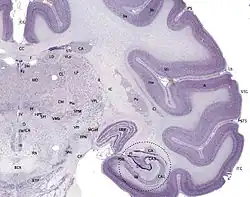

Nissl-stained coronal section of the brain of a macaque monkey, showing hippocampal formation and subfields (circled)

The hippocampus is sometimes called the hippocampus proper and just includes the CA subfields (cornu Ammonis 1-4). The hippocampus, dentate gyrus, and other subfields make up the hippocampal formation. The dentate gyrus contains the fascia dentata and the hilus. The CA is differentiated into subfields CA1, CA2, CA3, and CA4. CA4 is often not referred to since it has been shown to be the deep, polymorphic layer of the dentate gyrus.[37][38][39]